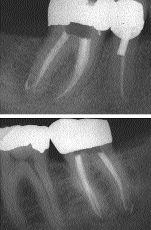

FIGURE 18--Mandibular molar with lateral canals filled in apical third of distal root.

There have been numerous articles written on instrumentation techniques, utilizing the different rotary nickel titanium files on the market. I have found that practitioners develop a system that works best in their own hands. Often this is a hybrid of several techniques discussed in various articles. After creating a clean, tapered canal, we now need … Read more